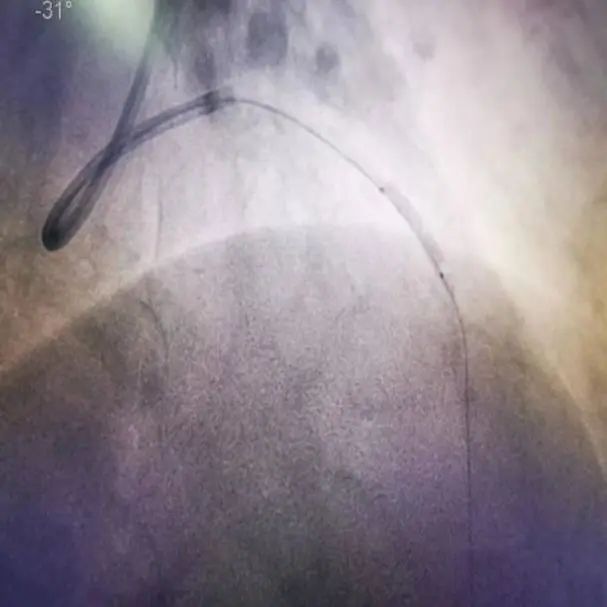

患者张先生,77岁,主因发作性胸痛、气短4天,加重2小时入院。入院诊断:冠状动脉性心脏病 急性前壁ST段抬高型心肌梗死 高血压病3级(很高危) 陈旧性脑梗死。冠脉造影显示冠脉前降支成角,迂曲,重度钙化,孙彦博教授团队在应用冠脉腔内影像学技术OCT对该血管进行了进一步的评估,结果显示:LAD近中段可见重度钙化,据此选择2.5×12mm Shockwave IVL冲击波球囊对近中段钙化病变进行4个周期的预处理,应用OCT进一步评估显示严重钙化处出现钙化断裂带,置入支架后取得很好的效果。

患者冠脉造影图像及OCT显示360°环形钙化